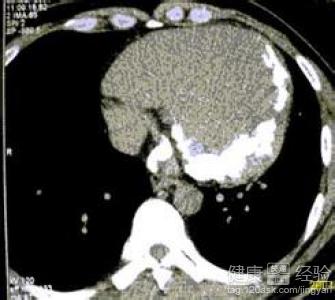

我今年已經有有三十五歲了,因為結婚的比較晚,所以我在去年四月份的時候才剖腹產生下了我的兒子,生完我兒子後我就感覺到精力變差了很多,但是最初我以為我只是月子沒有做好的關系。可直到最近一段時間,我在單位上班只要稍微感覺疲憊就會有呼吸困難的情況出現,到醫院檢查後,發現是患有了圍產期心肌病心髒變大疾病,那到底這個病可以治好嗎?

1該病的發生可能和女性在懷孕期間受到了病毒性的感染,或者是家族性的遺傳有一定的關系,通常發生在產後三個月內者最多,主要表現為呼吸困難、心悸、咳嗽、端坐呼吸、胸痛等心衰症狀。

2而女性一旦患有了該病後,擴大的心髒是不能夠在恢復到正常的狀態,所以,患者除了要積極配合醫生治療外,還應當避免再次妊娠,否則很容易出現了病症復發的情況發生,嚴重威脅到女性身體健康。

3目前在臨床上治療該病首選還是以為擴張血管的藥物以及強心的利尿劑為主,如果有栓塞的可以應用肝素,本病需堅持長期治療。只要患者能夠積極的配合醫生的治療,該病是可以達到徹底的治愈的目的,並且不會對患者的生命安全造成威脅。